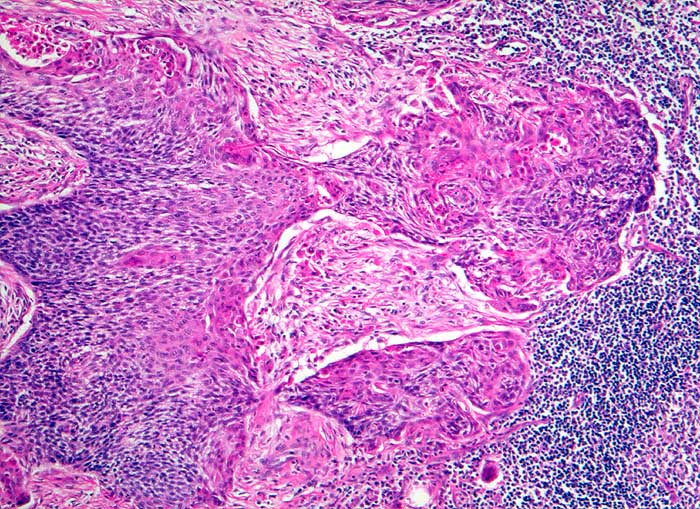

Lymphknotenmetastase: Plattenepithelkarzinom

Zervikale Lymphknotenmetastasen eines Plattenepithelkarzinoms stammen oft von Primärtumoren aus dem HNO Bereich. Diese sind im Unterschied zu den Plattenepithelkarzinomen der Lunge, die ebenfalls in die Halslymphknoten metastasieren, meist hoch differenziert, stark verhornend und ausgedehnt nekrotisch.